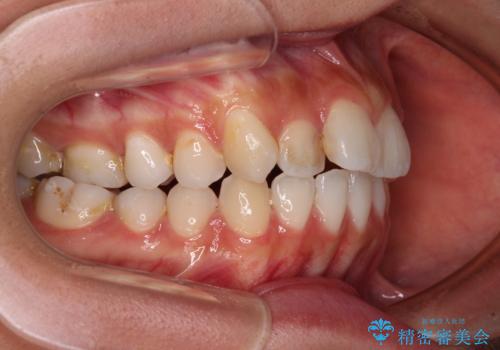

すきっ歯とオープンバイトをインビザラインで改善

- 前歯の上下スペースと前歯の隙間を気にして来院された患者様です。

インビザラインにより上下の前歯の隙間を閉じていくこととしました。

上下の隙間に舌が入り込むことが、すきっ歯やオープンバイトの原因であったため、舌の筋肉のトレーニングも並行して行い、後戻りの抑制を図りました。